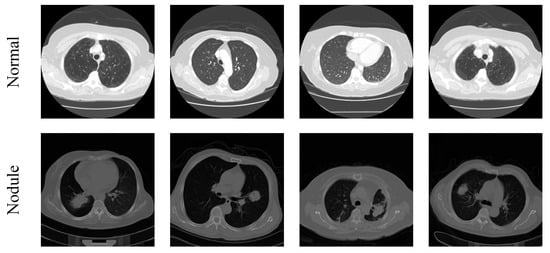

3.1. Image Database Preparation

| Image Class | Dimension | Total Images | Training Images | Validation Images |

| Normal | 224 × 224 × 3 | 1000 | 750 | 250 |

| Nodule | 224 × 224 × 3 | 1000 | 750 | 250 |